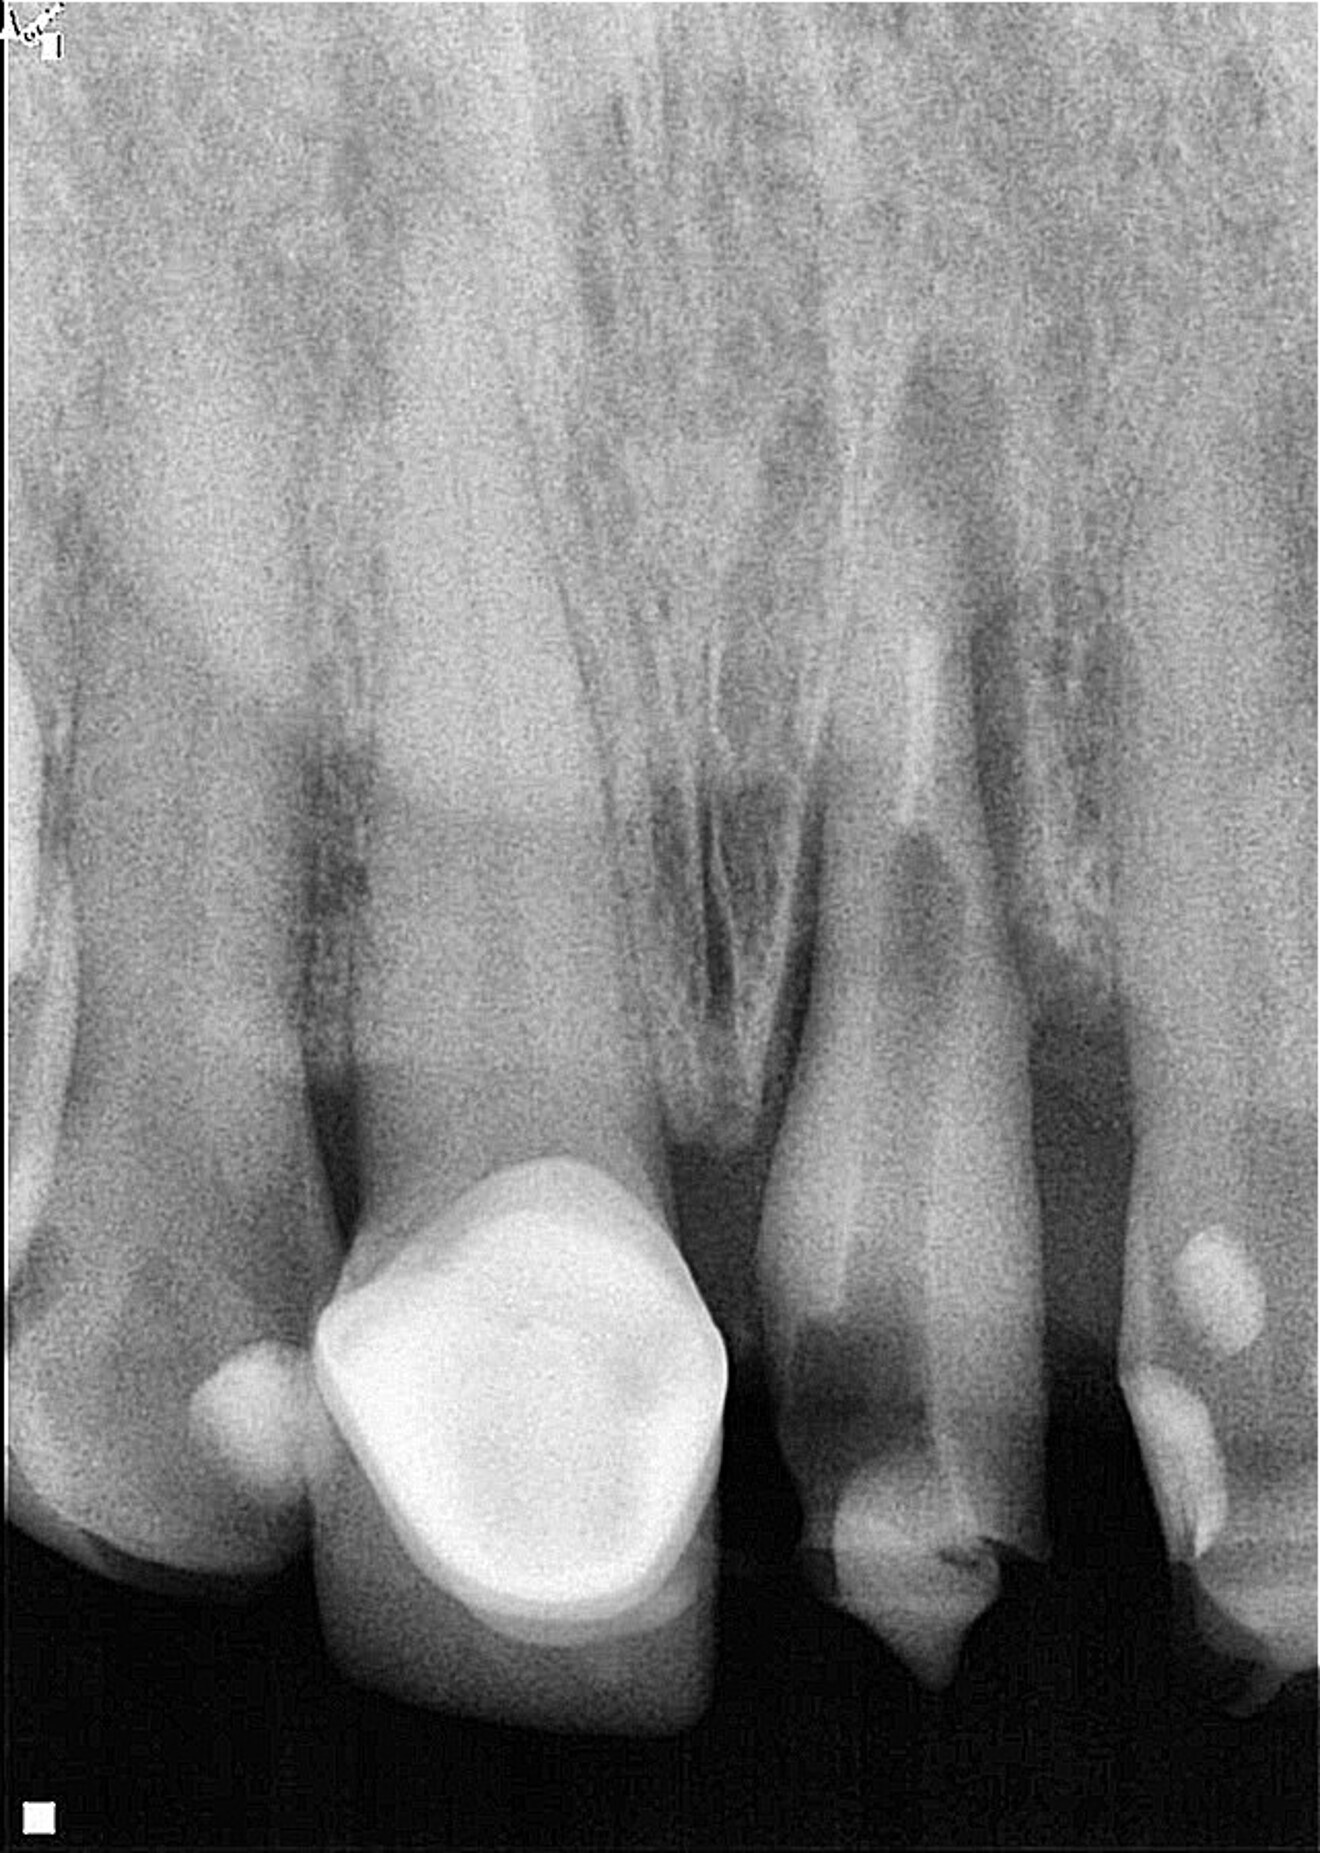

Fig. 3: Eight-week follow-up radiograph with the provisional crown in place showing bone remodelling of the mesial and distal aspects of the bone crest and periapical healing in progress.

The coronal preparation for the placement of a provisional crown was performed eight weeks after the surgical extrusion procedure. At that appointment, active bone remodelling, mainly at the periapical area, was observed (Fig. 3). This remodelling process is characterised by bone loss at the crestal area in the initial six to eight weeks postoperatively.16 The definitive restoration was placed three months after the initial procedure to provide enough time for the periodontal tissue to heal, thereby preventing post-restorative gingival migration.19, 2 Healthy periodontal tissue, good symmetry of the gingival margin and appropriate ferrule length were observed just before placement of the definitive restoration (Fig. 4).